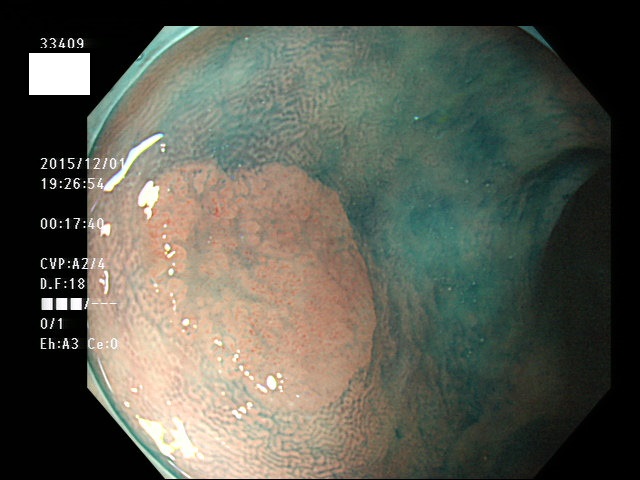

上記100名より抽出した平坦・陥凹型腺腫(=癌化の危険が高いが見落としやすい病変)の内視鏡写真